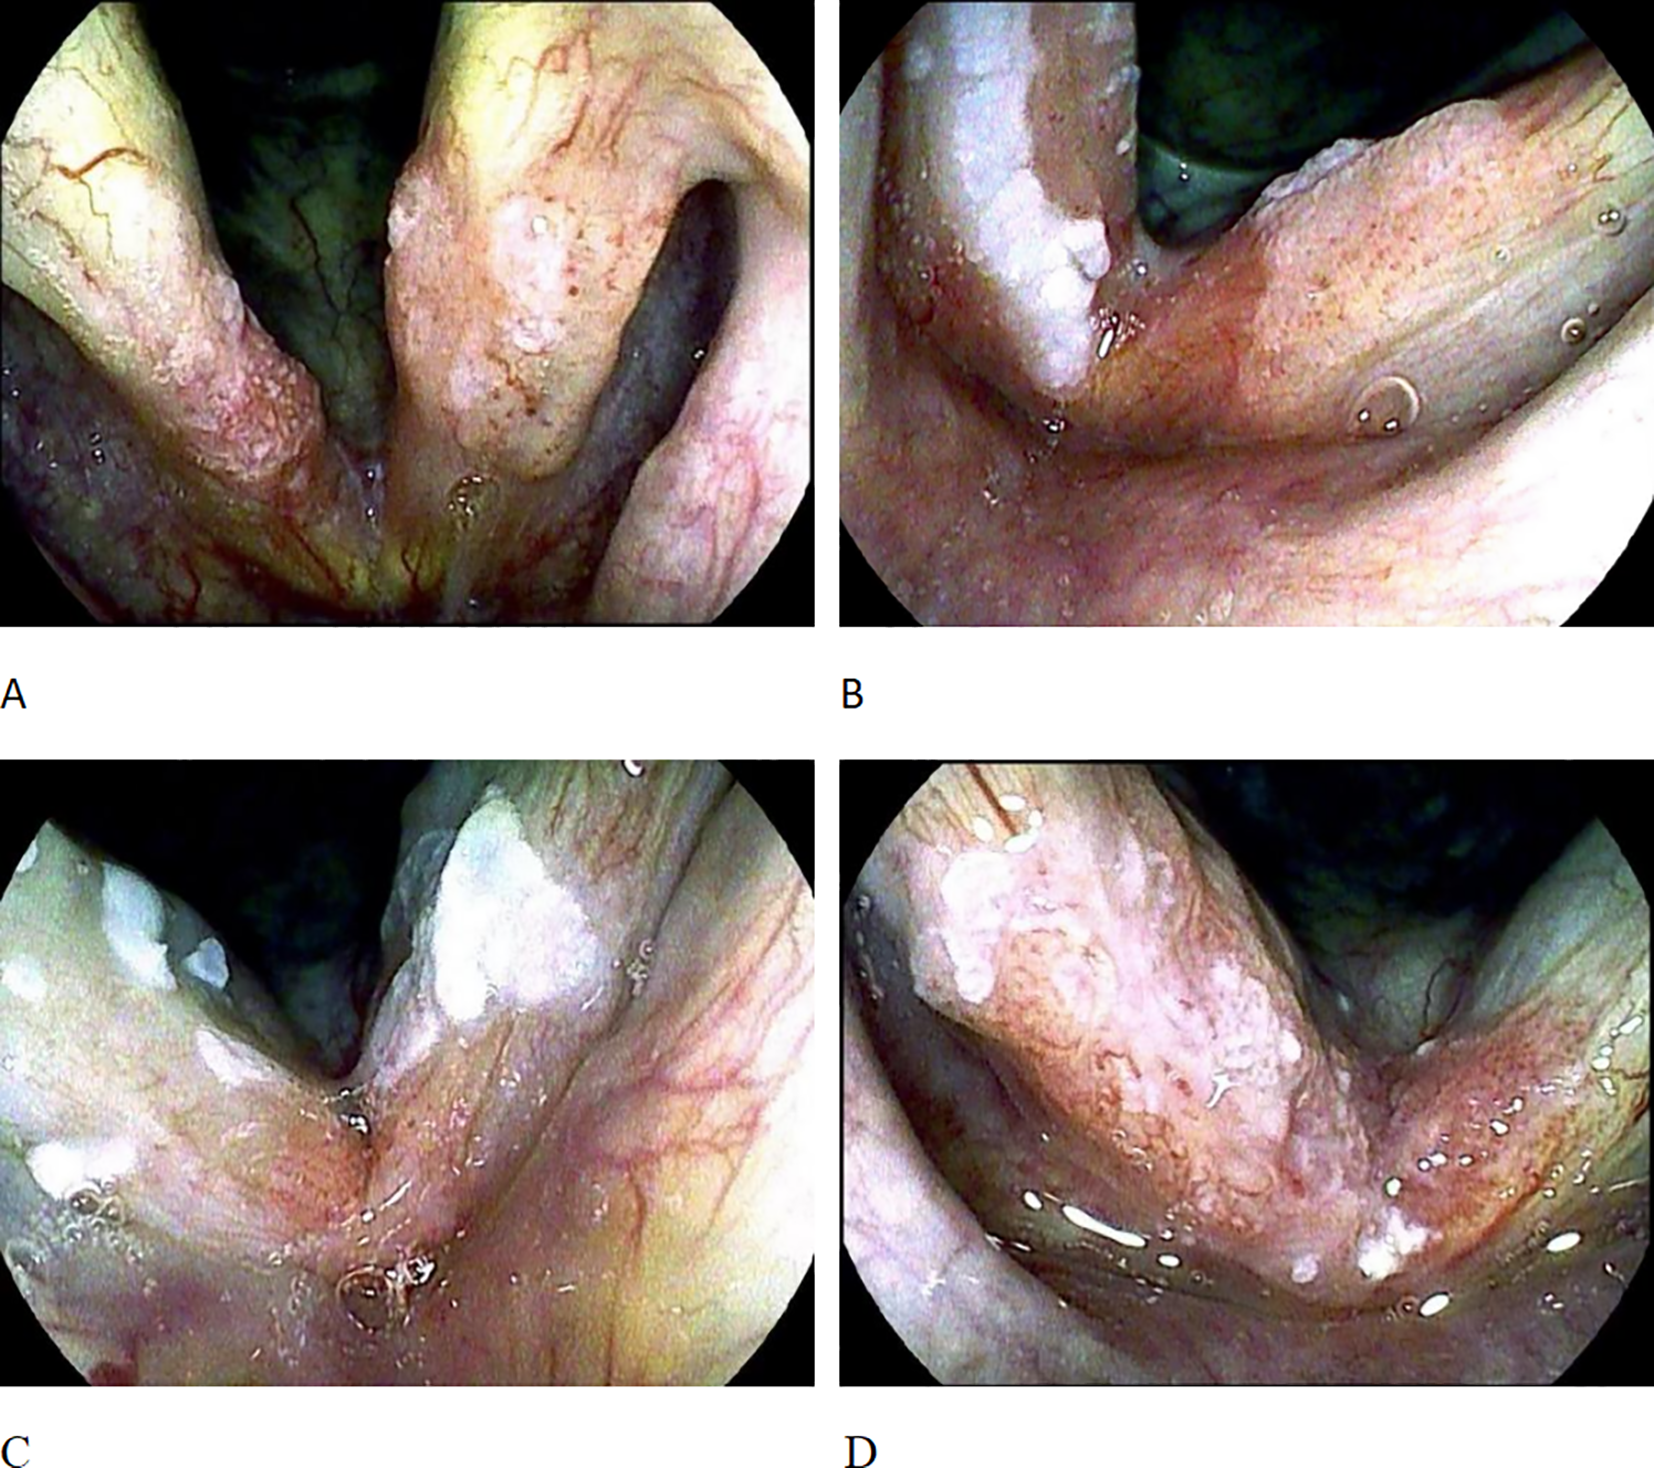

The TLM was performed under general endotracheal anesthesia. The old Sharplan 30C CO2 laser and the new AcuPulse30ST CO2 laser of Lumenis Corporation were successively used, with an output power of 3 - 8W in the super-pulse mode, and the operation was carried out under the Carl Zeiss surgical optical microscope. The tumor was resected along the safe margin (2 - 3mm) outside the edge of the tumor. For cases where preoperative pathological biopsy was not taken, tissue was first taken under the microscope for rapid frozen section pathological examination; for patients with pathologically confirmed laryngeal malignancies, the tumor was directly resected. The surgery was performed by a single surgeon using the “en bloc resection” or “piecemeal resection” technique according to the expansion and exposure of the tumor. The classification of vocal cord resection was based on the standards of the European Laryngological Society (ELS) (8, 9): type I, subepithelial; type II, subligamental; type III, transmuscular; type IV, total; type Va, encompassing the contralateral vocal fold and the AC; type Vb including the arytenoids; type Vc, encompassing the subglottis; type Vd, including the ventricle; and type VI, AC ectomy with bilateral anterior cordectomy. To prevent vocal cord adhesion, some patients received staged surgeries, laryngeal membrane implantation, and ventricular band mucosal flap repair. For T1a, Types II - Va vocal cord resection were adopted, and for T1b, Types II - VI vocal cord resection were used. Since 2016, a subset of patients have not undergone intraoperative frozen section analysis of surgical margins. Since 2019, the scope of the tumor was determined by preoperative examination with the image-enhanced endoscope i-scan of Pentax Corporation of Japan, and intraoperative frozen section analysis of surgical margins has not been performed. For patients with postoperative vocal cord adhesion, granulation residue, or partial local recurrence, secondary TLM treatment was performed. This study recorded the demographic characteristics (age and gender) of the patients, risk factors (smoking and drinking conditions), AC involvement, and postoperative vocal cord adhesion and granulation hyperplasia. Smoking habits were graded according to packs per year, and patients were divided into non-smokers or smokers with less than 20 packs per year (Light Smokers), smokers with 20 – 40 packs per year (Moderate Smokers), and smokers with more than 40 packs per year (Heavy Smokers). Ethanol exposure was graded according to the average daily ethanol intake, and patients were divided into those with no or minimal intake (Minimal Intake), those with mild to moderate intake (< 100 grams per day) (Moderate Intake), and those with heavy intake (> 100 grams per day) (Heavy Intake). All of the above factors were combined to determine the local control rate and disease-specific survival rate of the patients. The AC subarea classification referred to the classification proposed by Rucci et al. (10): AC0 indicated that both vocal cords were affected but the AC area was not involved; AC1 indicated that the AC area was only affected on one side of the midline; AC2 indicated that part of the AC area crossed the midline and was affected; AC3 indicated that the entire AC area was affected, and there were lesions on both the upper and lower surfaces of the AC (Figure 1).

Figure 1

AC staging. (A) shows AC0, with bilateral vocal cord lesions but the AC region not involved; (B) shows AC1, where the AC region is only involved on one side of the midline; (C) shows AC2, where the AC region is involved across the midline. (D) shows AC3, involvement of the whole anterior commissure subsite on both sides across the midline.